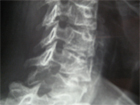

Cas clinique N°67

Dr Véra Lemaire Paris

Diagnostic et analyse des réponses

Le CR radiographique mentionnait des RX normales mais en fait sur le 3/4 droit il existait une lyse de l'arc postérieur de C7, ce qui témoignait d'une pathologie maligne. Sur le scanner thoracique il y avait une lésion du lobe supérieur droit dont la biopsie a montré qu'il s'agissait d'un adéno-carcinome bronchique.

Le scanner cervical a confirmé la lyse de l'arc postérieur s'étendant au corps vertébral dans sa moitié droite avec